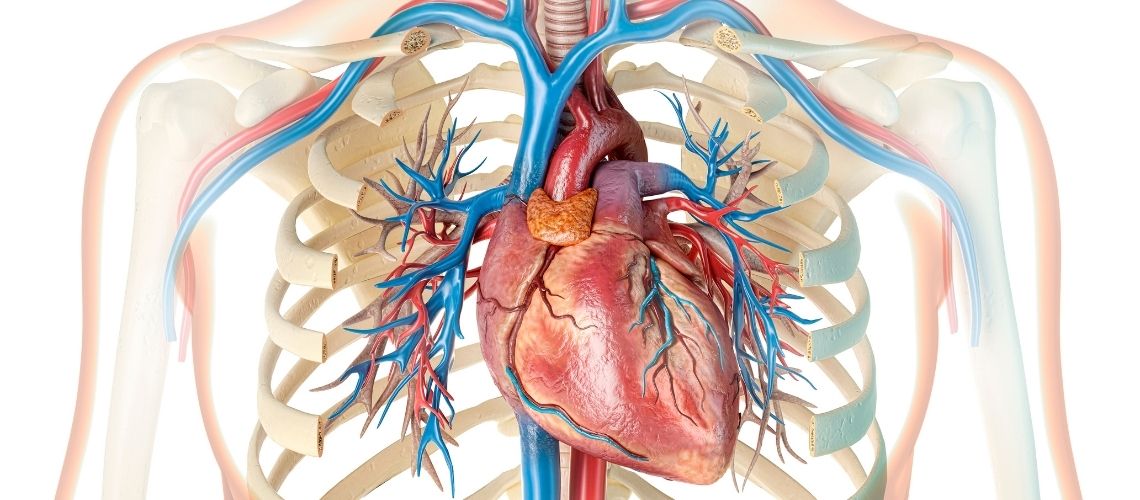

Kalp Krizi Sırasında Göğüste Ne Hissedilir?

Kalp krizinin en bilinen belirtisi göğüste hissedilen rahatsızlıktır. Bu genellikle göğsün ortasında bir baskı, sıkışma, ağırlık hissi veya ağrı şeklinde olur. Sanki göğsünüze biri oturmuş gibi hissedebilirsiniz. Bu his birkaç dakikadan uzun sürebilir veya gelip gidebilir. Bazen insanlar bunu mide yanması veya hazımsızlık gibi daha basit bir durumla karıştırabilirler. Ağrının şiddeti kişiden kişiye değişir; bazen çok şiddetliyken bazen şaşırtıcı derecede hafif olabilir.

Ağrı Vücudun Başka Yerlerine Yayılır mı?

Evet, göğüsteki bu rahatsızlık hissi veya ağrı başka yerlere de yayılabilir. En sık olarak omuzlara, kollara (özellikle sol kola, ama her iki kolda da olabilir), sırta, boyuna, çeneye doğru yayılım gösterir. Hatta bazı insanlar dişlerinde veya karnın üst kısmında bile ağrı hissedebilirler. Önemli bir nokta da şudur ki bazen göğüste belirgin bir rahatsızlık olmadan sadece bu yayılan ağrılar da kalp krizinin belirtisi olabilir.

Nefes Darlığı ve Diğer Belirtiler Neler Olabilir?

Göğüs rahatsızlığı ve yayılan ağrı dışında başka belirtiler de görülebilir. Nefes darlığı sık karşılaşılan bir durumdur. Kişi birden nefes almakta zorlanmaya başlayabilir, nefesi kesilebilir veya sürekli derin nefes alma ihtiyacı duyabilir. Bu göğüs ağrısı olsun veya olmasın ortaya çıkabilir. Aniden başlayan soğuk terleme, bulantı hissi veya kusma, baş dönmesi, sersemlik veya bayılacak gibi hissetmek de diğer önemli işaretlerdir. Açıklanamayan ani ve aşırı yorgunluk hissi, bir endişe hali veya kötü bir şey olacakmış gibi bir his de eşlik edebilir.

Kalp Krizi ile Kalp Durması (Kardiyak Arrest) Aynı Şey midir?

Hayır, aynı şey değildirler ama birbiriyle ilişkilidirler. Kalp krizi bir “dolaşım” sorunudur. Kalbi besleyen damar tıkanır ve kalp kası hasar görür. Bu sırada kalp genellikle atmaya devam eder ve kişi çoğunlukla bilinçlidir. Kardiyak arrest (kalp durması) ise bir “elektriksel” sorundur. Kalbin elektriksel sistemindeki bir arıza nedeniyle kalp aniden durur. Kişi hemen bilincini kaybeder ve nefesi durur. Ancak bir kalp krizi, kalbin elektriksel sistemini bozarak ani kalp durmasına yol açabilir. Bu nedenle her kalp krizi, potansiyel bir kalp durması riski taşır.